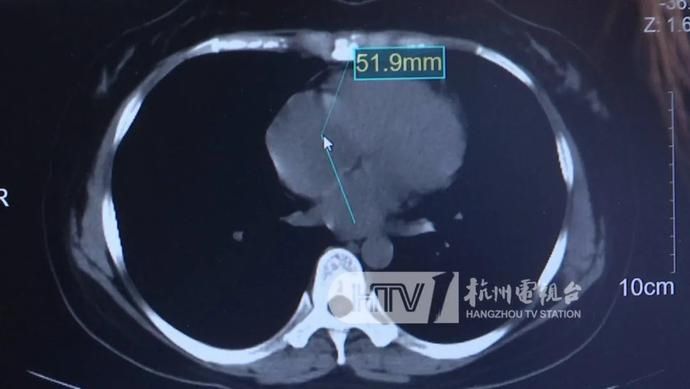

这一块是我们的右心房,直径也就四五厘米的样子,但是这位病人来就诊的时候,肿瘤直径已经超过6厘米了,已经超过了整个心房的大小。

不仅如此,肿瘤甚至已经侵犯到心脏上方的大血管,影响到了全身的血液循环,这也导致李女士出现了心脏衰竭,最典型的症状就是胸闷气急,和肺炎特别相似。